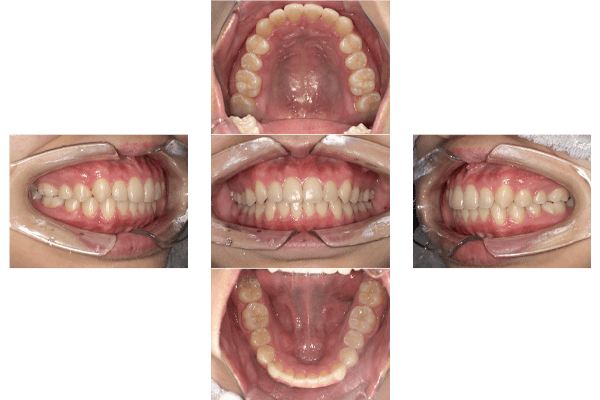

| 主訴 | 下の前歯のガタガタが気になる |

|---|---|

| 診断 | 受け口+叢生(ガタガタ) |

| 治療期間 | 1年8カ月 |

| 治療費用 | 矯正費用¥792,000(税込) +補綴費用924,000(税込) +ホワイトニング |

| リスクと副作用 |

|

| 院長コメント | マウスピース矯正で受け口を直すために顎間ゴム(上あごと下あごにまたがるゴム)をかけてもらいました。また、上あごと下あごの真ん中もずれていたので顎間ゴムでそろえました。 下のがたつきもきれいに治ったのでご本人も大変満足されておりました。矯正治療終了後かぶせ物や詰め物をやり替え、スムーズに全体治療を終えることができました。矯正治療中にホワイトニングも行い、歯並びと歯の色、両方改善できて大変喜んでもらえました。 |